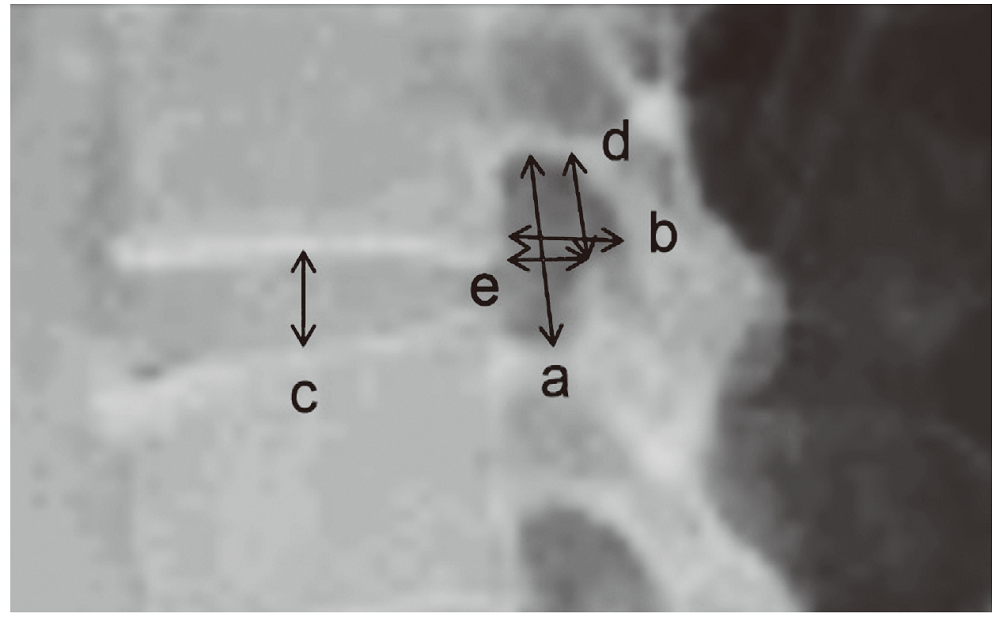

本文以延边朝鲜族正常成年人下腰椎椎间孔X射线测量数值为研究对象,行测量及对比,为不同民族人种经椎间孔入路脊柱内镜手术治疗提供相关数据。选取符合测量标准的腰椎X光片,对下腰椎椎间孔参数进行测量,结果行统计学分析并与国内外相关数据对比。延边朝鲜族正常成年男性和女性下腰椎椎间孔形态无明显差异,延边朝鲜族正常成年人下腰椎椎间孔测量数据与国内外学者测量的下腰椎椎间孔数据比较均存在差异。对不同地区民族人群施行腰椎微创手术,术前下腰椎椎间孔形态的个体化测量是必要的。

The lower lumbar foramina of normal Korean Yanbian adults were studied in this paper, with measurements taken through X-ray film providing comparative data for endoscopic spinal surgery for different ethnic groups. The statistically analyzed results showed no significant difference in the morphology of the lower lumbar foramina between normal adult males and females, while the significant differences were found between this research and other researches.